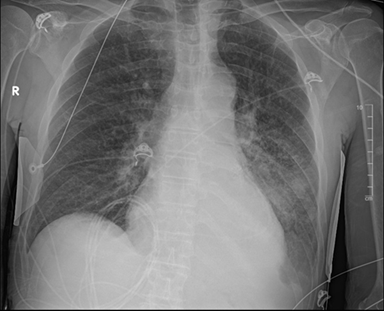

Figure 4. First cxr

post-discharge; left subclavian chest port with the tip in the svc. The heart

is stable in size. There is pulmonary venous congestion without overt edema.

Redemonstrated is a large mass like opacity in the left lower lobe with a small

left pleural effusion. No pneumothorax. The right lung is clear.

Upon discharge, he was educated on the importance of taking

his medications for copd, specifically his albuterol and ipratropium

nebulizers. Four days after discharge from our facility, he received a

single-lumen power port vascular catheter through the left subclavian vein for

chemotherapy. An outpatient cxr showed mild pulmonary venous congestion without

overt edema with a stable, large, mass-like opacity in the left lower lobe. Our

patient was given close follow up with hematology-oncology, pulmonology, and

primary care to optimize his management for stage iva nsclc.